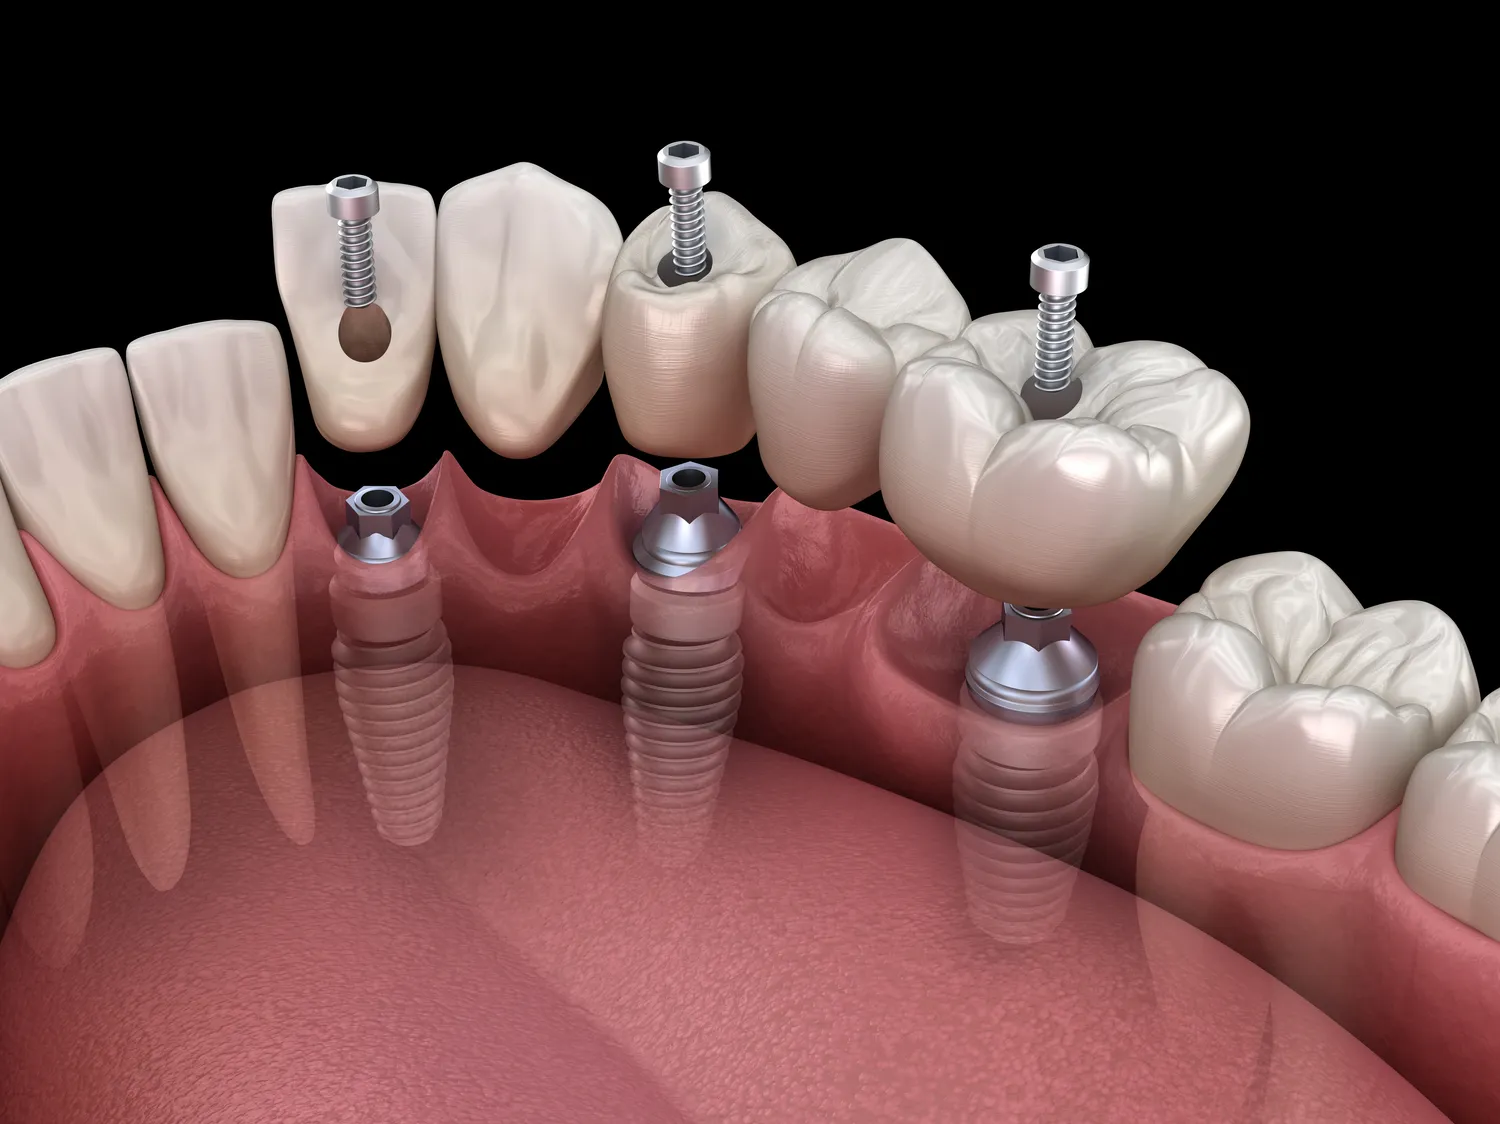

W ramach protetyki cyfrowej w Szczecinie dostępnych jest wiele rodzajów protez, które można dostosować do indywidualnych potrzeb pacjentów. Jednym z najpopularniejszych rozwiązań są korony i mosty protetyczne, które mogą być wykonywane zarówno na zębach naturalnych, jak i implantach. Korony pełnoceramiczne cieszą się dużym zainteresowaniem ze względu na swoją estetykę oraz trwałość. Innym rodzajem są protezy całkowite oraz częściowe, które stosuje się w przypadku braku jednego lub kilku zębów. Protezy te mogą być mocowane na implantach lub być klasycznymi rozwiązaniami opartymi na błonie śluzowej jamy ustnej. Warto również wspomnieć o nakładkach ortodontycznych, które są coraz częściej wykorzystywane w leczeniu wad zgryzu. Dzięki technologii cyfrowej możliwe jest ich precyzyjne zaprojektowanie oraz wykonanie, co zwiększa komfort noszenia i skuteczność leczenia.

Proces leczenia w protetyce cyfrowej w Szczecinie rozpoczyna się od konsultacji stomatologicznej, podczas której lekarz ocenia stan uzębienia pacjenta oraz omawia jego potrzeby i oczekiwania. Po przeprowadzeniu szczegółowego wywiadu oraz badania klinicznego następuje etap skanowania jamy ustnej za pomocą specjalistycznego urządzenia. Skanowanie to pozwala na uzyskanie trójwymiarowego obrazu zębów i tkanek miękkich, który następnie jest przesyłany do oprogramowania CAD. Tam lekarz projektuje odpowiednią protezę zgodnie z anatomicznymi wymaganiami pacjenta. Po zatwierdzeniu projektu przez pacjenta następuje produkcja protezy przy użyciu technologii druku 3D lub frezowania komputerowego. Po wykonaniu protezy odbywa się kolejna wizyta kontrolna, podczas której lekarz dokonuje przymiarek oraz ewentualnych poprawek. Ostatecznie po zaakceptowaniu przez pacjenta gotowego produktu następuje jego osadzenie w jamie ustnej.

W protetyce cyfrowej w Szczecinie wykorzystuje się szereg nowoczesnych technologii, które znacząco poprawiają jakość i efektywność leczenia. Jednym z kluczowych elementów jest skanowanie 3D, które pozwala na dokładne odwzorowanie struktury jamy ustnej pacjenta. Dzięki temu lekarze mogą uzyskać precyzyjny obraz zębów, co jest niezbędne do dalszego projektowania protez. Skanery 3D są niezwykle zaawansowane i potrafią uchwycić nawet najdrobniejsze detale, co przekłada się na lepsze dopasowanie protez. Kolejną istotną technologią jest oprogramowanie CAD/CAM, które umożliwia projektowanie oraz produkcję protez w sposób zautomatyzowany. Dzięki temu proces staje się szybszy i bardziej precyzyjny. Oprogramowanie to pozwala również na symulację końcowego efektu, co daje pacjentowi możliwość zobaczenia, jak będą wyglądały jego nowe zęby przed ich wykonaniem. Dodatkowo, technologie druku 3D oraz frezowania komputerowego są wykorzystywane do produkcji protez, co zapewnia wysoką jakość materiałów oraz estetykę finalnego produktu.